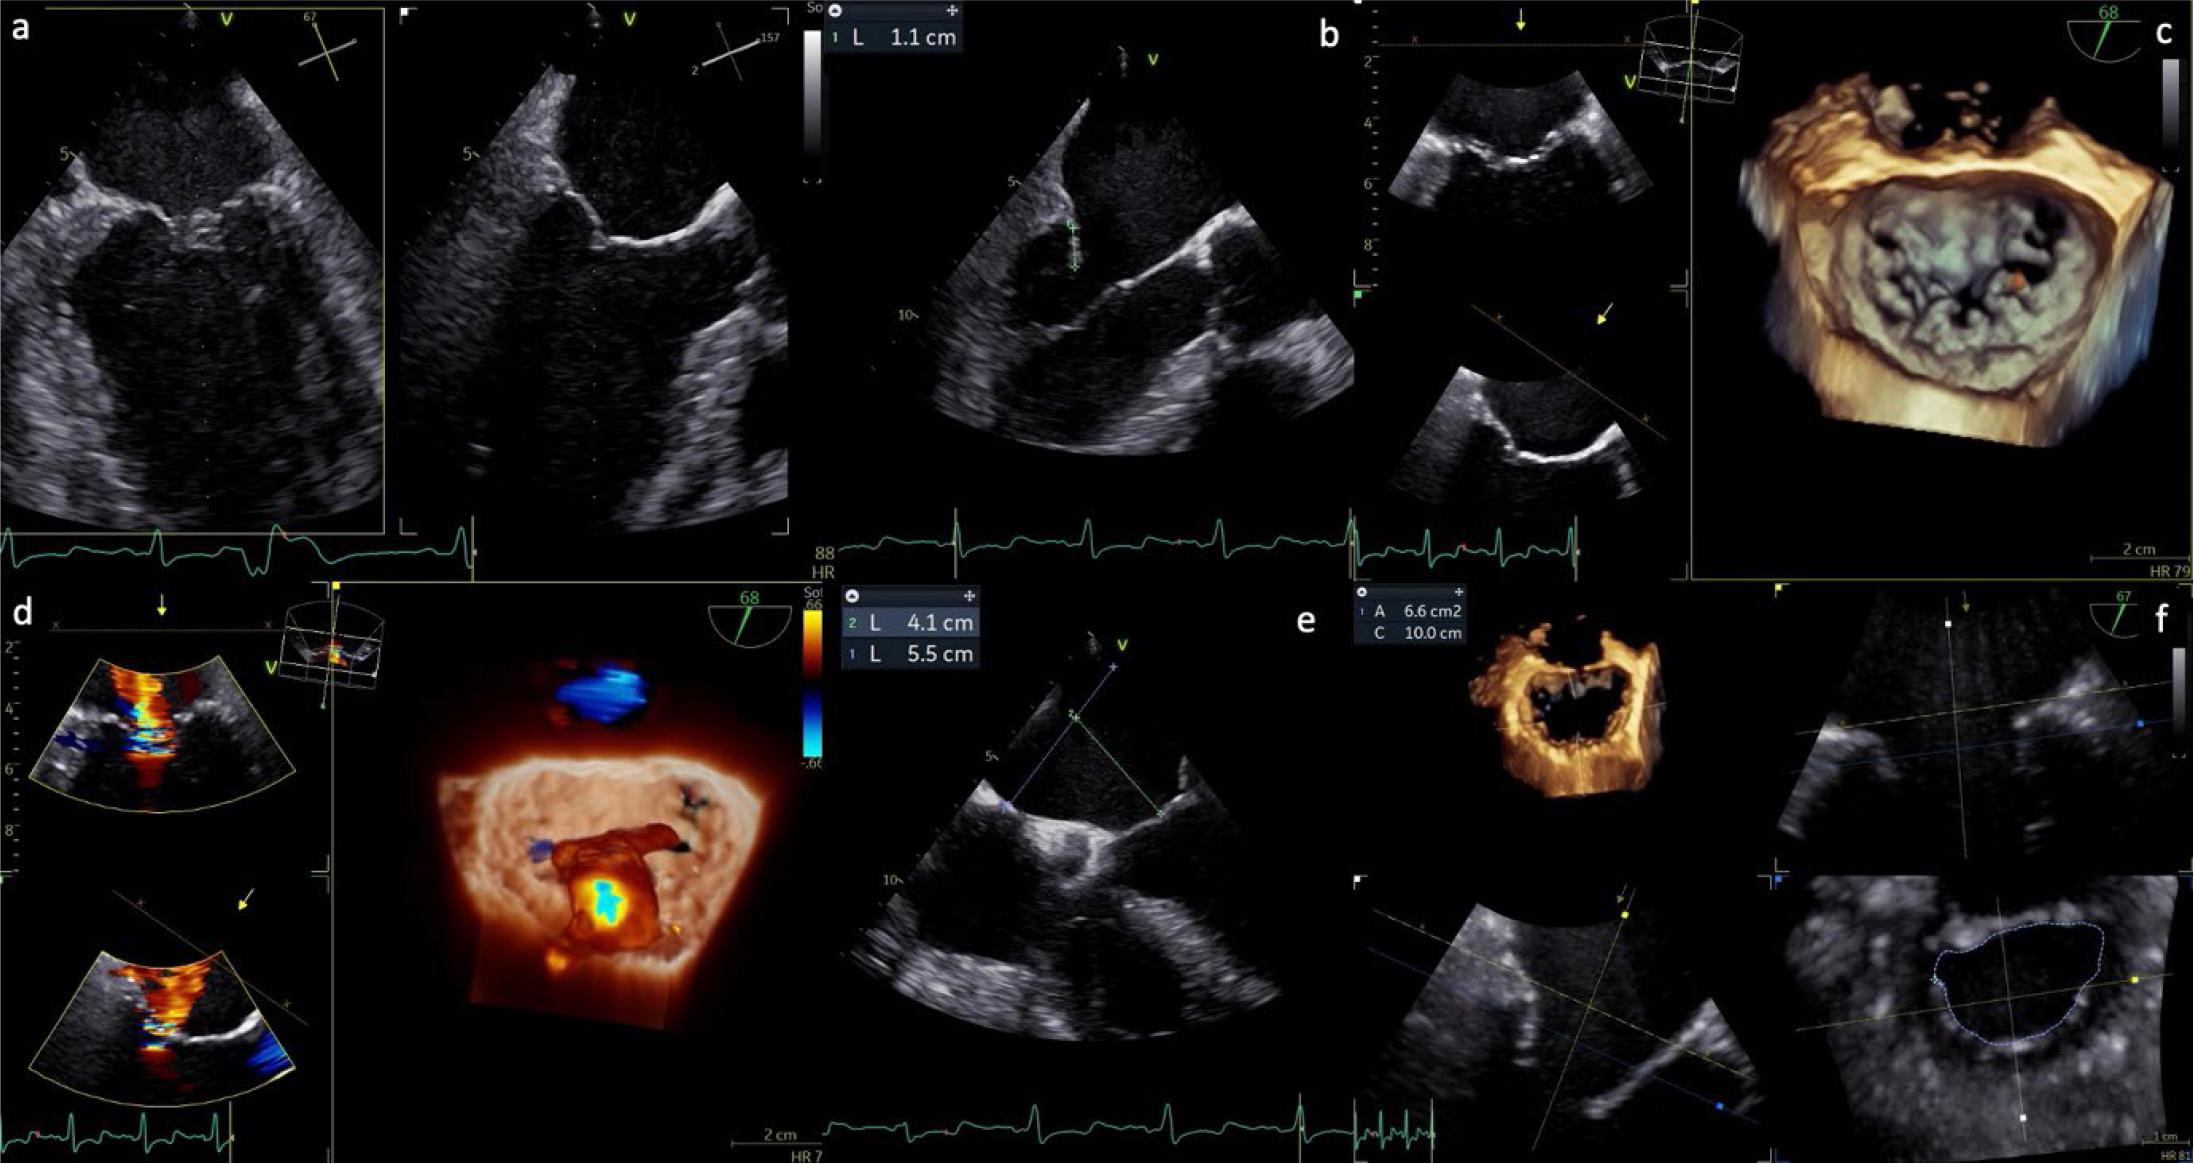

A comprehensive imaging workup is central to the diagnostic, therapeutic, and procedural planning pathway in patients considered for TEER. Transthoracic echocardiography (TTE) remains the cornerstone for the initial assessment, providing essential information on MR severity, mechanism, and hemodynamic consequences, including estimates of pulmonary artery pressures, biventricular function, and concomitant valvular lesions. However, due to its superior spatial resolution and ability to visualize leaflet anatomy and motion in detail, transesophageal echocardiography (TOE)— preferably with three-dimensional (3D) capabilities—is mandatory in almost all TEER candidates to determine anatomical suitability (Figure 2).

Preprocedural TOE assessment in a case of SMR. (a) X-plane bicommissural and LV long-axis view (67°/157°); (b) measurement of the posterior leaflet, showing adequate length for device grasping; (c) 3D reconstruction of the mitral valve, en face (surgical) view; (d) 3D reconstruction demonstrating severe SMR due to leaflet restriction, with a centrally originating jet directed posteriorly; (e) evaluation of septal puncture feasibility; (f) multiplanar reconstruction (MPR) for calculation of the anatomical MVA.

In the context of SMR, accurate assessment of regurgitation severity presents notable challenges. A comprehensive evaluation (Figure 2) using a multiparametric and integrative approach is essential, incorporating qualitative, semiquantitative, and quantitative echocardiographic indicators.[2] Quantitative thresholds traditionally associated with severe MR include a vena contracta (VC) width ≥ 7 mm, regurgitant fraction ≥ 50%, EROA ≥ 40 mm2, and RV ≥ 60 mL.[2] However, in SMR, reliance on EROA and RV—typically derived using the proximal isovelocity surface areamethod—can be misleading, as the assumptions of a circular regurgitant orifice and stable flow may not hold true. The regurgitant orifice is often elliptical, and low-flow states common in advanced LV dysfunction can further distort these measurements. As a result, lower thresholds (e.g., EROA ≥ 30 mm2 and RV ≥ 45 mL) are frequently proposed to define severe MR in SMR populations.[2i Nonetheless, such cutoffs must be interpreted in clinical context, since modeling studies suggest they may correspond to unrealistically low cardiac outputs. [64,73] Therefore, the integration of advanced imaging parameters, such as 3D VC measurements, alongside indirect markers—such as systolic flow reversal in pulmonary veins, LA dilatation, LV systolic function and diameter, evidence of pulmonary hypertension, and signs of right ventricular dysfunction—remains critical for accurate grading and therapeutic decision-making in SMR.

TEE enables a meticulous evaluation of mitral valve morphology, including leaflet thickness, mobility, prolapse or tethering, clefts, and calcification—particularly within the intended grasping zone of the clip arms.[64,73]

Precise anatomical assessment (Figures 2,3) is fundamental in the preprocedural evaluation of patients with MR considered for transcatheter repair. The flail gap—the vertical distance from the ventricular aspect of the flail leaflet segment to the atrial edge of the opposing leaflet—is measured during systole, perpendicular to the annular plane, using TOE views in the four-chamber long axis and LV outflow tract (LVOT). The flail width, defined as the extent of the flail segment along the coaptation line, is typically assessed in transgastric short-axis or commissural views. Identifying calcification within the grasping zone (approximately the distal 7 mm of both anterior and posterior scallops) is essential to distinguish it from leaflet thickening or fibrosis, which may affect device anchoring. Additional measurements such as coaptation length (the leaflet overlap) and coaptation depth (the apical displacement of leaflet meeting point relative to the mitral annulus) further inform anatomical suitability— especially in secondary MR. Key quantitative thresholds, including a flail gap <10 mm, flail width <15 mm, and coaptation depth <11 mm, are instrumental for procedural planning in degenerative MR, while also aiding risk stratification in functional cases (Figure 3).[(64] Moreover, three-dimensional multiplanar reconstruction (3D MPR) plays a critical role in delineating jet origin and quantifying the VC area, which are predictors of procedural success and long-term durability.

Following leaflet grasping, residual MR must be carefully evaluated, and transmitral gradients should be measured to exclude significant iatrogenic mitral stenosis. Insights from prior device generations provide useful benchmarks regarding the expected reduction in the MVA postimplantation. For instance, the PASCAL P10 system has been reported to reduce MVA by approximately 47%. Importantly, the extent of this reduction is strongly influenced by the device’s position along the coaptation line, with the greatest decrease occurring when the device is deployed centrally at the A2/P2 scallops—often referred to as the “hot zone”—and a more modest reduction is observed with commissural placement. Beyond the implantation site, the location of the regurgitant jet and the chosen therapeutic approach are critical determinants in selecting the appropriate device and strategy. In cases involving multiple jets, where two devices may need to be placed at a considerable distance from one another, a baseline MVA of at least 6 cm2 is generally advised to avoid inducing clinically significant mitral stenosis (Figure 4).